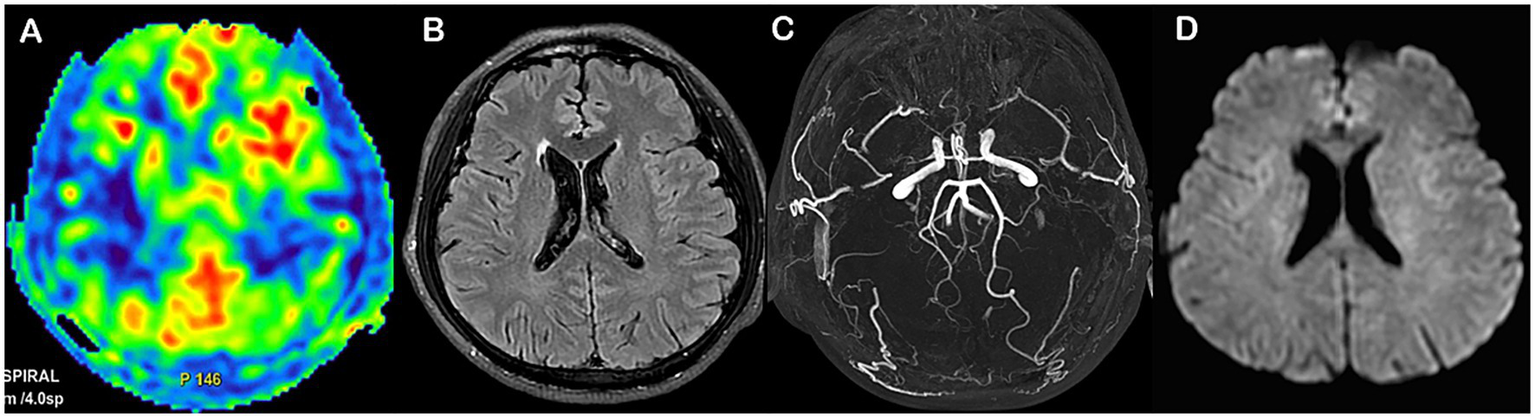

Representative patients with MMD with poor and good prognoses are shown in Figures 6, 7, respectively.

Figure 6

Representative MMD case with poor prognosis (A–D). Female, 60 years old, with an admission mRS score of 2, and an mRS score of 3 after 1 year. T2-FLAIR showing ivy sign (A); Preoperative ASL-ASPECT score was 4 (B). Houkin score was 6 at 1 week postoperatively, and MRA staging was stage 3 (C); DWI showing acute/subacute infarction in the right caudate nucleus (D). The nomogram score was 130, with a probability of poor prognosis of 0.90.